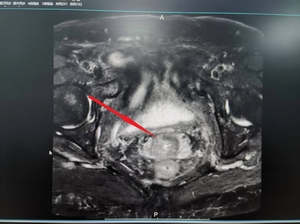

▲插植完成后行CT扫描,显示插植针位置与肿瘤完全吻合

▲计划优化完成后的剂量分布图(100%的剂量包围了整个肿瘤,对正常组织进行了有效保护,大大减少了正常组织的副反应)